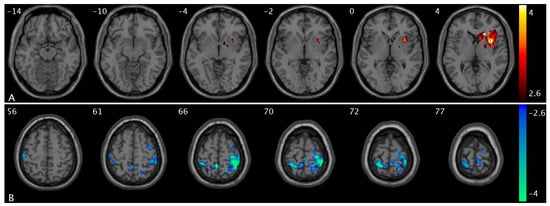

We observed significant changes in PCC FC from low- to high-urge states in healthy controls and OAB participants separately. Specifically, when bladder filling increases from low- to high-urge states, we found PCC FC increases in the superior frontal, superior medial frontal, insula, putamen, caudate, middle temporal, and middle occipital regions in healthy controls (Figure 3A and Figure S1C) but no PCC FC changes in these regions in OAB participants; and PCC FC decreases in the postcentral and superior parietal regions (i.e., sensorimotor network area) in healthy controls (Figure 3B) but there are no PCC FC changes in these regions in OAB participants. A summary of the clusters’ statistics is reported in Table S1.

Figure 3. Statistical maps overlaid on T1-weighted images showing altered PCC FC from low- to high-urge state in healthy controls and OAB participants. (A) PCC FC increases in insula, putamen, and caudate in healthy controls (within the same slice range as in Figure 1C); (B) PCC FC decreases in the postcentral and superior parietal regions in healthy controls. Additional increased PCC FC regions are shown in Figure S1C. The numbers in the top left corner of the MRI images indicate the z-coordinate (in mm) in the MNI space. The color bars represent t-values.